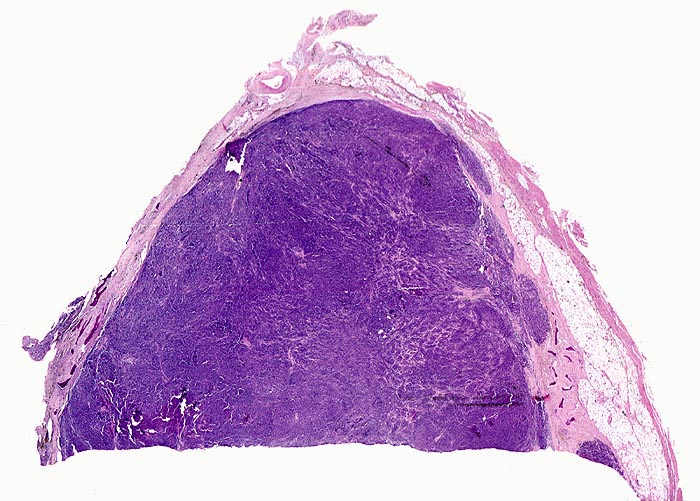

• Knochenmarkstanze mit nodulärer Hyperzellularität des blutbildenden Marks.

• Keine wesentliche Osteopenie.

• In den hyperzellulären Arealen dichte Rasen neoplastischer atypischer Plasmazellen.

• Ausserhalb der Plasmazellrasen findet sich spärlich residuelles blutbildendes Knochenmark.